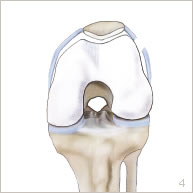

L’intervention consiste à recentrer la rotule dans la gorge trochléenne afin de lui redonner un jeu harmonieux.

Elle est réalisée sous arthroscopie, c’est à dire sans ouvrir l’articulation. Deux petites incisions de 5 mm chacune sont réalisées en avant du genou. Une petite caméra est introduite par l’une d’entre elles pour visualiser l’articulation. Des petits instruments sont introduits par l’autre incision pour sectionner l’aileron (figures 3 et 7).